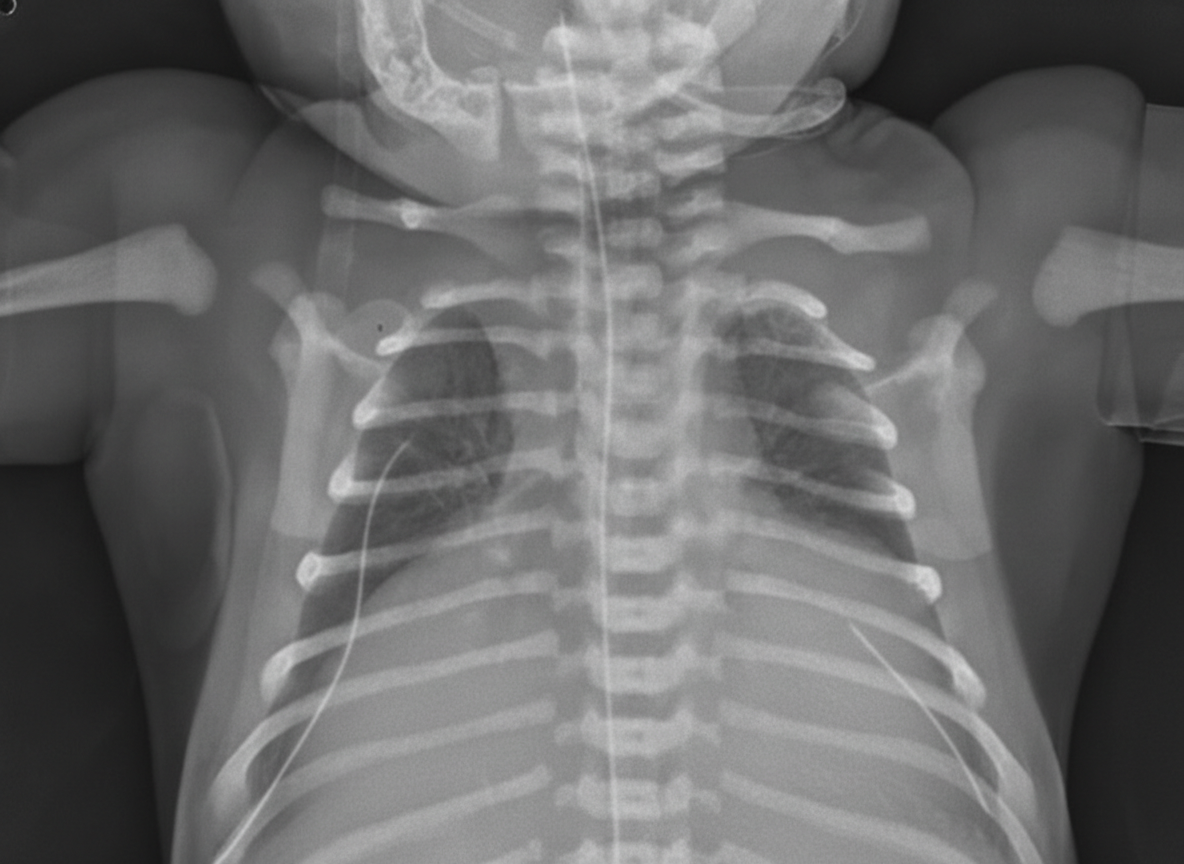

A 2-hours-old neonate is found to have bluish discoloration throughout his body, including lips and tongue. The boy was born at 39 weeks gestation via spontaneous vaginal delivery with no prenatal care. Maternal history is positive for type 2 diabetes mellitus for 11 years. On physical examination, his blood pressure is 55/33 mm Hg, his heart rate is 150/min, respiratory rate is 45/min, temperature of 37°C (98.6°F), and oxygen saturation is 84% on room air. Appropriate measures are taken. Auscultation of the chest reveals a single second heart sound without murmurs. Chest X-ray is shown in the exhibit. Which of the following is the most likely diagnosis?